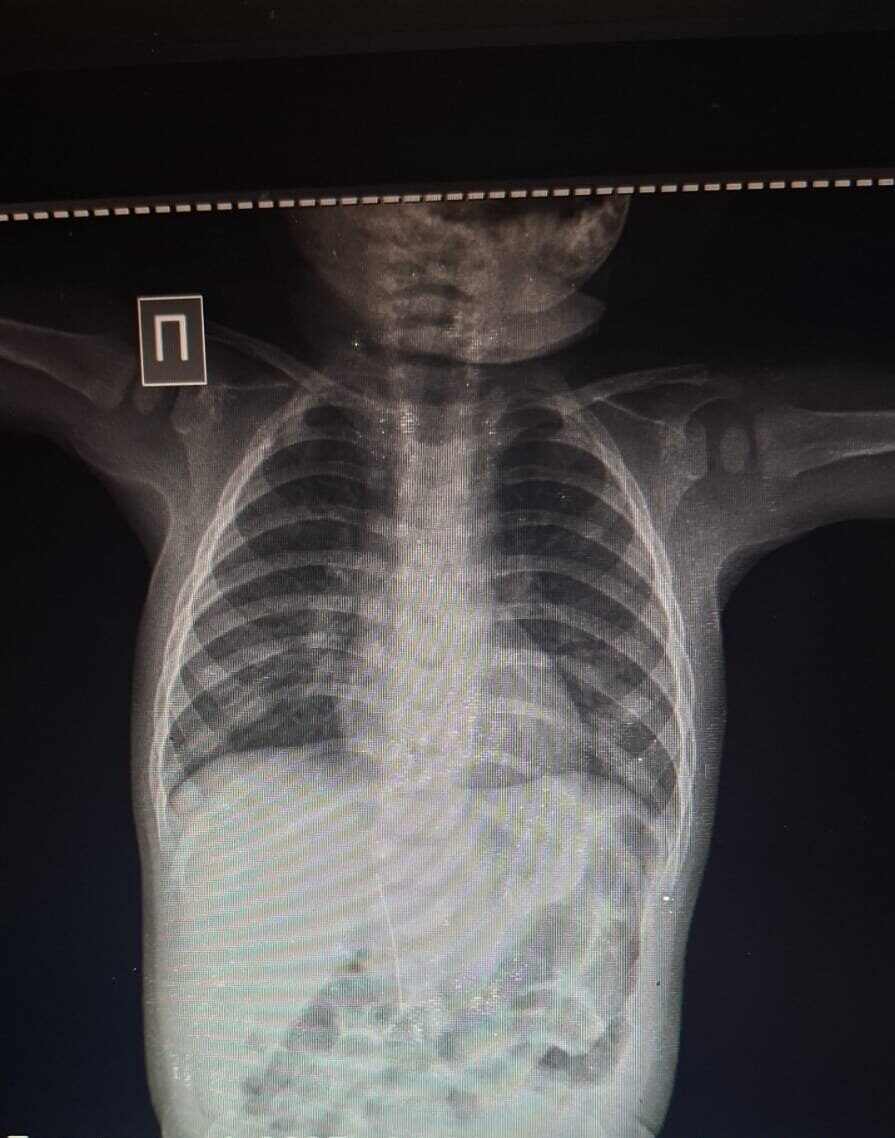

Во время обследования врачи провели рентгенологическое исследование, результаты которого шокировали даже опытных специалистов: в брюшной полости младенца была обнаружена игла. Как выяснилось позже, именно она стала причиной высокой температуры и постоянного беспокойства ребенка, а не инфекция.

По словам медиков, инородный предмет попал в организм не через пищеварительный тракт. Игла проникла со стороны области печени. Родители и врачи исключают возможность того, что ребенок мог проглотить ее самостоятельно.